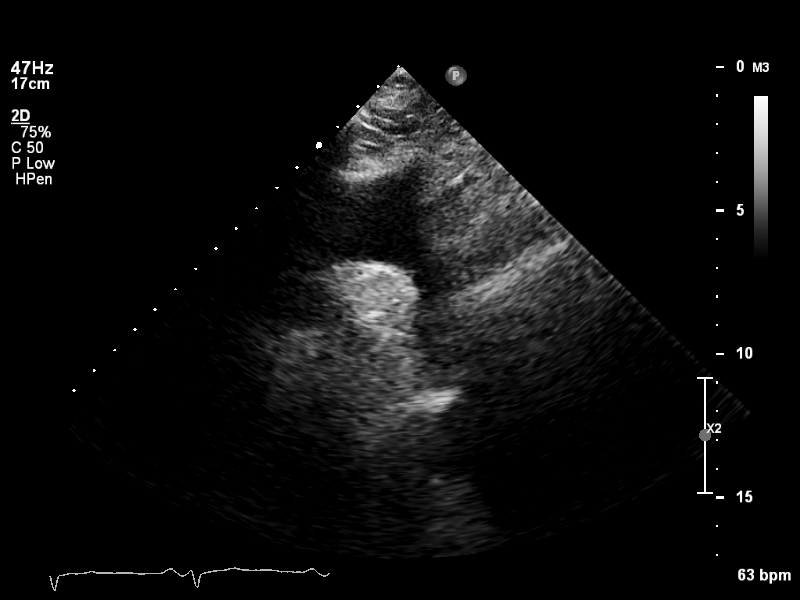

ImageView NameDescription

plax-full-la plax-full-la Parasternal long-axis, sector covers whole LA; intended for LA measurements

plax-full-lv plax-full-lv PLAX with imaging sector covering LV but not the whole LA

plax-full-mv plax-full-mv PLAX centered on MV (heavy zoom losing LA/LV parts or MV colour)

plax-full-out plax-full-out Zoomed-out PLAX

plax-full-rv-ao plax-full-rv-ao Focus on RV & aorta or colour Doppler over RV/AV/Aorta

plax-tv plax-tv Parasternal inflow view including tricuspid valve

plax-valves-av plax-valves-av PLAX focused on the aortic valve

plax-valves-mv plax-valves-mv PLAX focused on the mitral valve